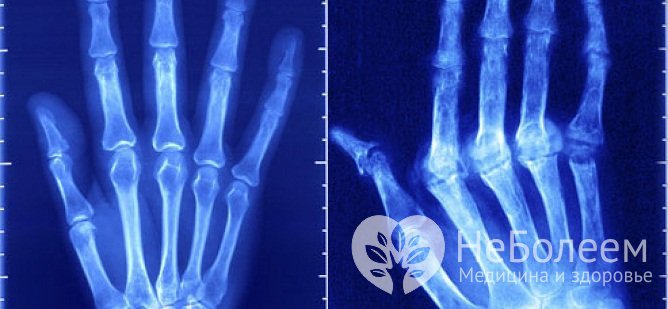

Стадии артритаКлиническая картина артрита пальцев рук отличается большой вариабельностью и зависит от этиологической формы и стадии болезни. Ранней стадии ревматоидного артрита свойственна скованность суставов по утрам и после длительного покоя. При этом возникает характерное ощущение тугих перчаток, ограничивающих подвижность кисти. В отдельных случаях у пациента может вовсе не быть жалоб, а единственными проявлениями заболевания служат ранние рентгенологические признаки артрита пальцев рук:

Характерные признаки воспаления суставов пальцев, как правило, наблюдаются на II стадии заболевания, начиная с появления болезненной припухлости, эритемы и крепитации в пораженных суставах, а к рентгенологическим признакам прибавляются множественные сужения межсуставных щелей, кистовидные просветления костной ткани и краевые деформации эпифизов костей. Вывихи, подвывихи и анкилозы суставов выявляют преимущественно на терминальных стадиях заболевания.

В ходе сбора анамнеза врач обращает внимание на связь манифестаций артрита с перенесенными ранее инфекционными заболеваниями, метаболическими и соматическими патологиями, а также с воздействием повреждающих факторов. При физикальном осмотре ценным источником диагностической информации становятся размер, форма и температура суставов, цвет кожных покровов, характер болезненных ощущений, функциональные пробы, наличие внесуставных проявлений и т. д. Иногда необходимы консультации других специалистов – ортопеда-травматолога, дерматолога и аллерголога-иммунолога. Выявление характерных изменений в суставах пальцев требует применения инструментальных методик – рентгенографии, МРТ и КТ кистей, УЗИ мелких суставов.

Артрит пальцев рук на рентгеновском снимкеЛабораторная диагностика играет решающую роль для установления причины воспалительной реакции. Общий анализ крови достоверно выявляет признаки воспалительного процесса. В ходе биохимического анализа крови определяется уровень мочевой и сиаловой кислоты, позволяющий подтвердить либо исключить диагноз подагрического артрита. Высокие показатели ревматоидного фактора и C-реактивного белка, фибриногена, серомукоида, криоглобулинов и т. д. указывают на ревматоидную патологию. В отдельных случаях показано лабораторное исследование пунктата синовиальной жидкости.